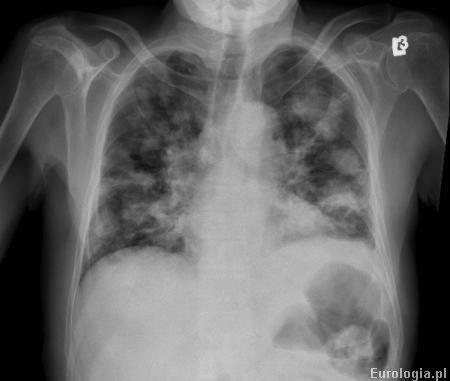

Określenie meta jest skrótem od łacińskiego słowa metastasis oznaczającego przerzut. Rozpoznanie przerzutów stawiane jest na podstawie zdjęcia RTG klatki piersiowej lub tomografii komputerowej klatki.

Fot. Przerzuty do płuc u pacjenta z guzem nerki.